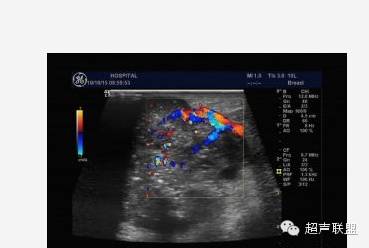

5.多普勒灵敏度和功率多普勒技术的改善,使观察乳腺内部的血管分布更为直接。在20世纪80年代初多普勒超声技术刚用于血管检测时,主要采用连续波多普勒,因为它有较高的灵敏度。乳腺肿块周围的血管内含有较高的血流速度被认为是恶性肿瘤的象征。现在,只需用彩色多普勒观察分布于肿块内外的血管数量即可作出同样的诊断。尽管对于多普勒信息的解释仍有异议,但多数研究者及ATL/FDA临床实验的结果确认了乳腺肿块中增加的血管分布预示了恶性肿瘤。

声像图表现:于右乳腺相当于六点钟,距约1.5cm处见一大小约1.0x0.6cm低回声肿物,边界尚清,形态不规,周边可检出动脉频谱样血流信号,RI为0.67,余腺体回声粗糙,未见占位性病变。右腋下另见数个淋巴结,较大的为1.4x0.8cm,边界清,周边呈低回声,中心部呈高回声。

签别诊断:主要是和乳腺Ca的签别,癌肿内还可以有“沙粒样”的微钙化灶,浆细胞性乳腺炎的病灶内血管多为低阻力型,RI一般小于0.70;乳腺癌的病灶内血管一般为高阻力型,RI多数大于0.70。(其机理是由于肿瘤血管在解剖结构上缺乏肌层,且没有一般血管从近端到远端逐渐变细的特点,导致局部受压,使血管阻力升高;而浆细胞性乳腺炎则无上述特点)。当图象上两者有交叉不好区分时,结合病史是最关键的,浆细胞性乳腺炎既往可有红、肿、热、痛的病史,急性期和亚急性期的结节有触痛,常有导管扩张,慢性期的结节可存在数年之久,抗生素治疗无效时,应想到本病的可能性;乳腺癌患者常无症状,仅触及包块,病史短,不伴导管扩张。